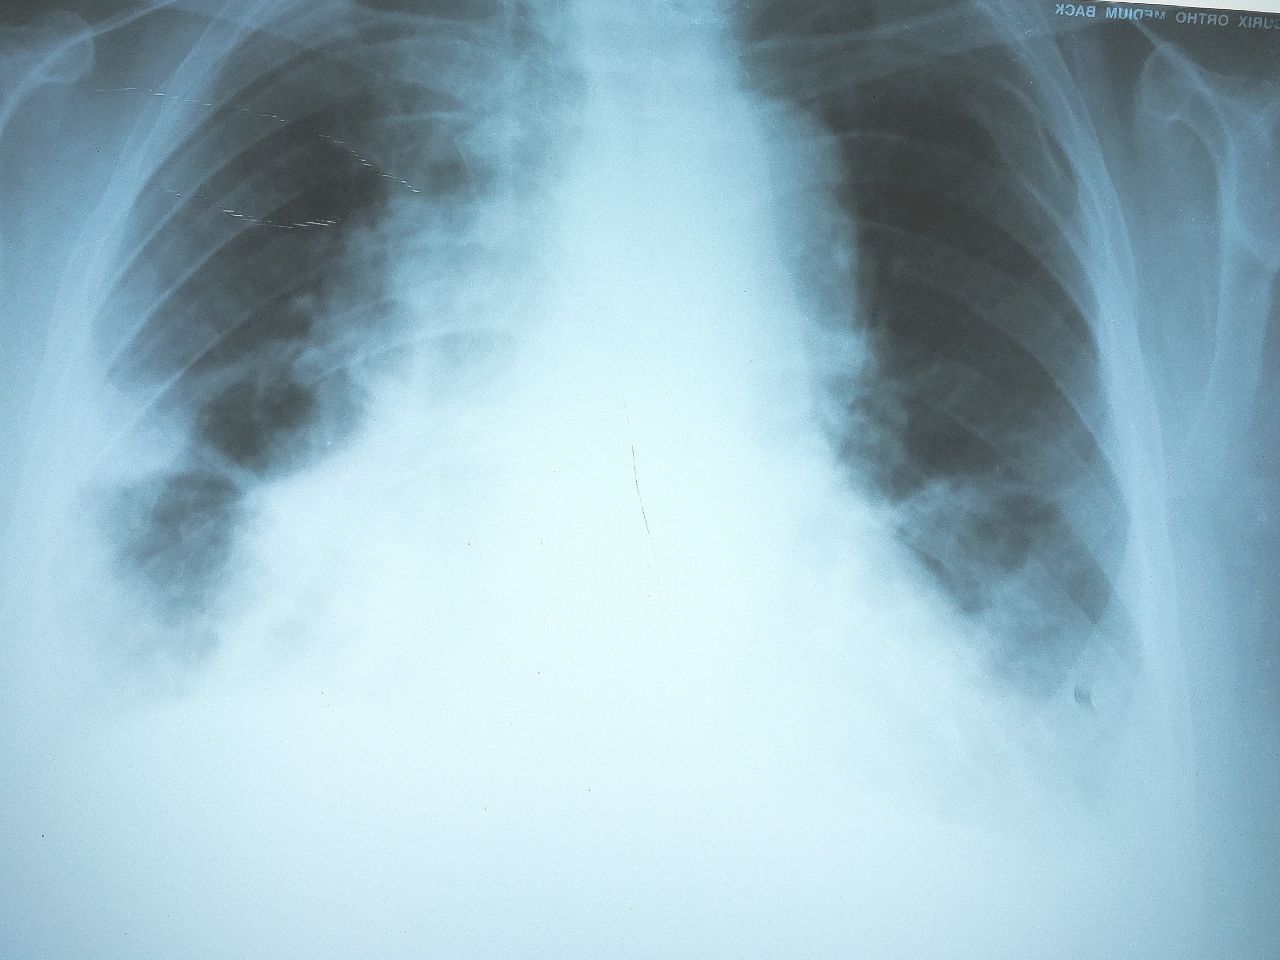

Подскажите, бабушка 76 лет, температуры нету, только задышка, проблемы с сердцем. Пневмонию без температуры можно ставить по даному снимку или только застойные явления, шварта справа и гидроторакс?

хсн

Ковид базально-латеральная пневмония